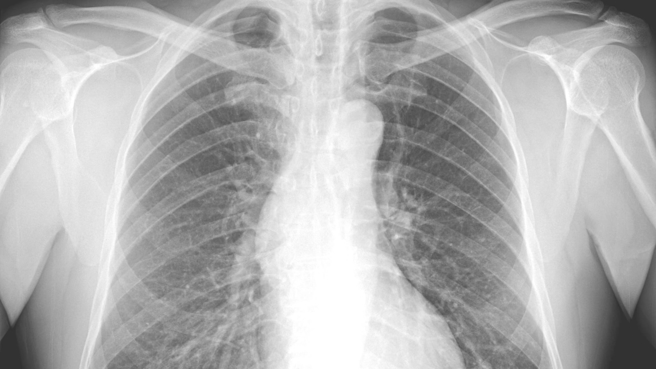

苏一峰今(9)日于个人脸书指出,一名50多岁的男子进入诊间就开始咳嗽、吸鼻水,主诉痰多,他认为男子症状和新冠肺炎相似,再加上肺部X光片也有明显肺炎,他建议男子应该要做新冠肺炎筛检。

男子表示,同住家人也有和他有相同症状,苏一峰听完,语带不悦地说,「你这个状况,有很高的机率是新冠,且全家都有症状,你的肺部X光片也是肺炎,怎么不先做快筛检验?」男子下一秒无奈抱怨,「因为我买不到快筛啊!」苏一峰直呼,这就是感染黑数,不验就不会确诊。